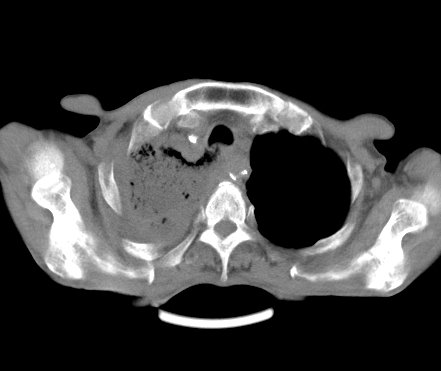

以下是引用深泽交通医院在2008-5-25 9:53:00的发言:[br]右肺炎症;纵隔淋巴结肿大,考虑转移;左侧术后胸腔胃

以下是引用gaoshengjiang在2008-5-30 19:53:00的发言:[br]右上叶可见大片实变影,其内可见充气支气管影及囊状影,右上叶尖端支气管走形区可见结节样影,左侧胸腔内可见胸腔胃影。纵隔淋巴结肿大。[br]考虑:1.右上肺阻塞性肺炎伴肺脓肿形成。支持转移所致。[br] 2.左侧胸腔胃。